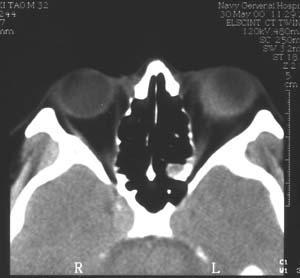

眼球内炎症有感染性、非感染性、肉芽肿性和非肉芽肿性。其中以感染性的眼内炎(多为非肉芽肿性)和肉芽肿性的交感性眼炎最为严重。